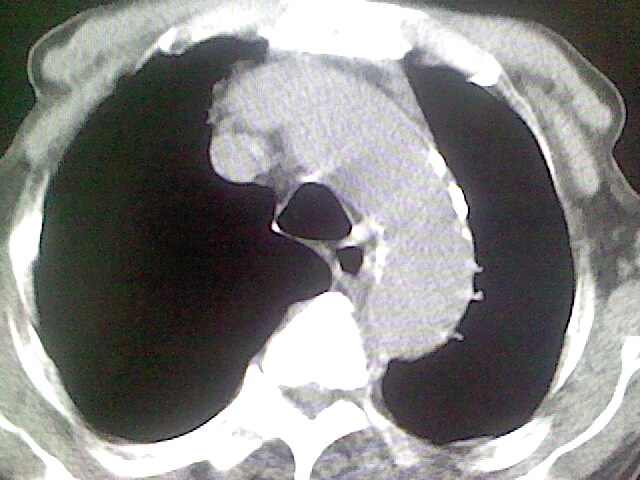

以下是引用zsl6918在2008-8-28 16:49:00的发言:[br]双肺炎性病灶,食管狭窄估计与心房增大压迫所致。

以下是引用xulianj在2008-8-28 20:36:00的发言:[br]慢支肺气肿伴感染,右上肺陈旧性结核;食道建议胃镜检查。

以下是引用wqs571018在2008-8-28 21:18:00的发言:[br]慢支继发感染,右上肺陈旧性结核;食道建议胃镜检查。